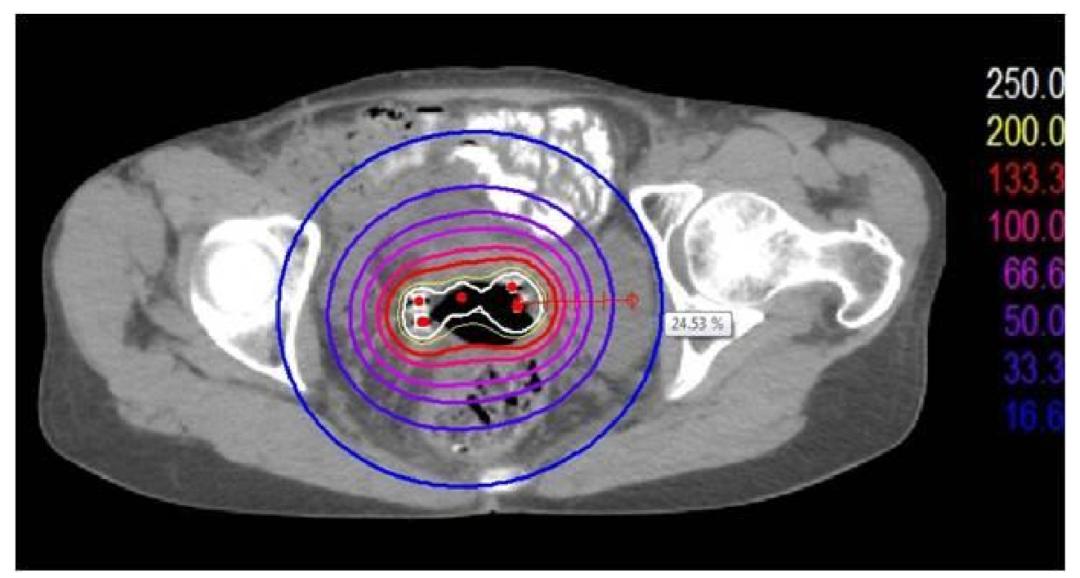

图2

图3

图2-3:[标准的近距离放疗的剂量图及DVH图,剂量图提示:组织的受照剂量与距离放射源的远近呈反比,距离放射源越近,受照剂量越高,距离放射源越远,受照剂量越低(白色圈内的红色点为放射源分布位置,10%~300%的放疗剂量依次用蓝色至白色的彩色圈表示,放射源近处的白色线圈为处方剂量的300%受照范围,距离放射源4cm以上的蓝色圈为处方剂量的10%受照范围,提示组织受照剂量可由处方剂量的300%急速跌落至10%);DVH图横轴为受照剂量,纵轴为受照的靶区体积,靶区的线图在100%的处方剂量之后拖出一个长长的尾巴,提示95%靶区受到100%的放疗剂量,但这95%靶区体积受到的放射剂量高达100%~300%,最高剂量在300%以上]